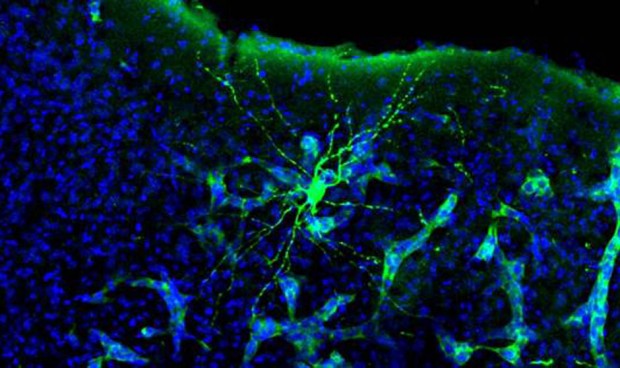

Los autores, del Consejo Superior de Investigaciones Científicas (CSIC) y el Centro Nacional de Investigaciones Oncológicas (CNIO), han descubierto que cuando el cáncer se disemina en el cerebro (hace metástasis) altera la química cerebral, e interfiere así en la comunicación neuronal. Las neuronas se comunican mediante impulsos eléctricos que se generan y transmiten mediante cambios bioquímicos en las células y su entorno.

Además de registrar los cambios en la actividad eléctrica cerebral en presencia de metástasis, los investigadores han empezado a explorar los cambios bioquímicos que explicarían esta alteración. Analizando los genes que se están expresando en los tejidos afectados han identificado una molécula, EGR1, con un papel potencialmente importante en el proceso. El hallazgo abre la posibilidad de diseñar un fármaco que prevenga o palíe los efectos neurocognitivos de la metástasis cerebral.